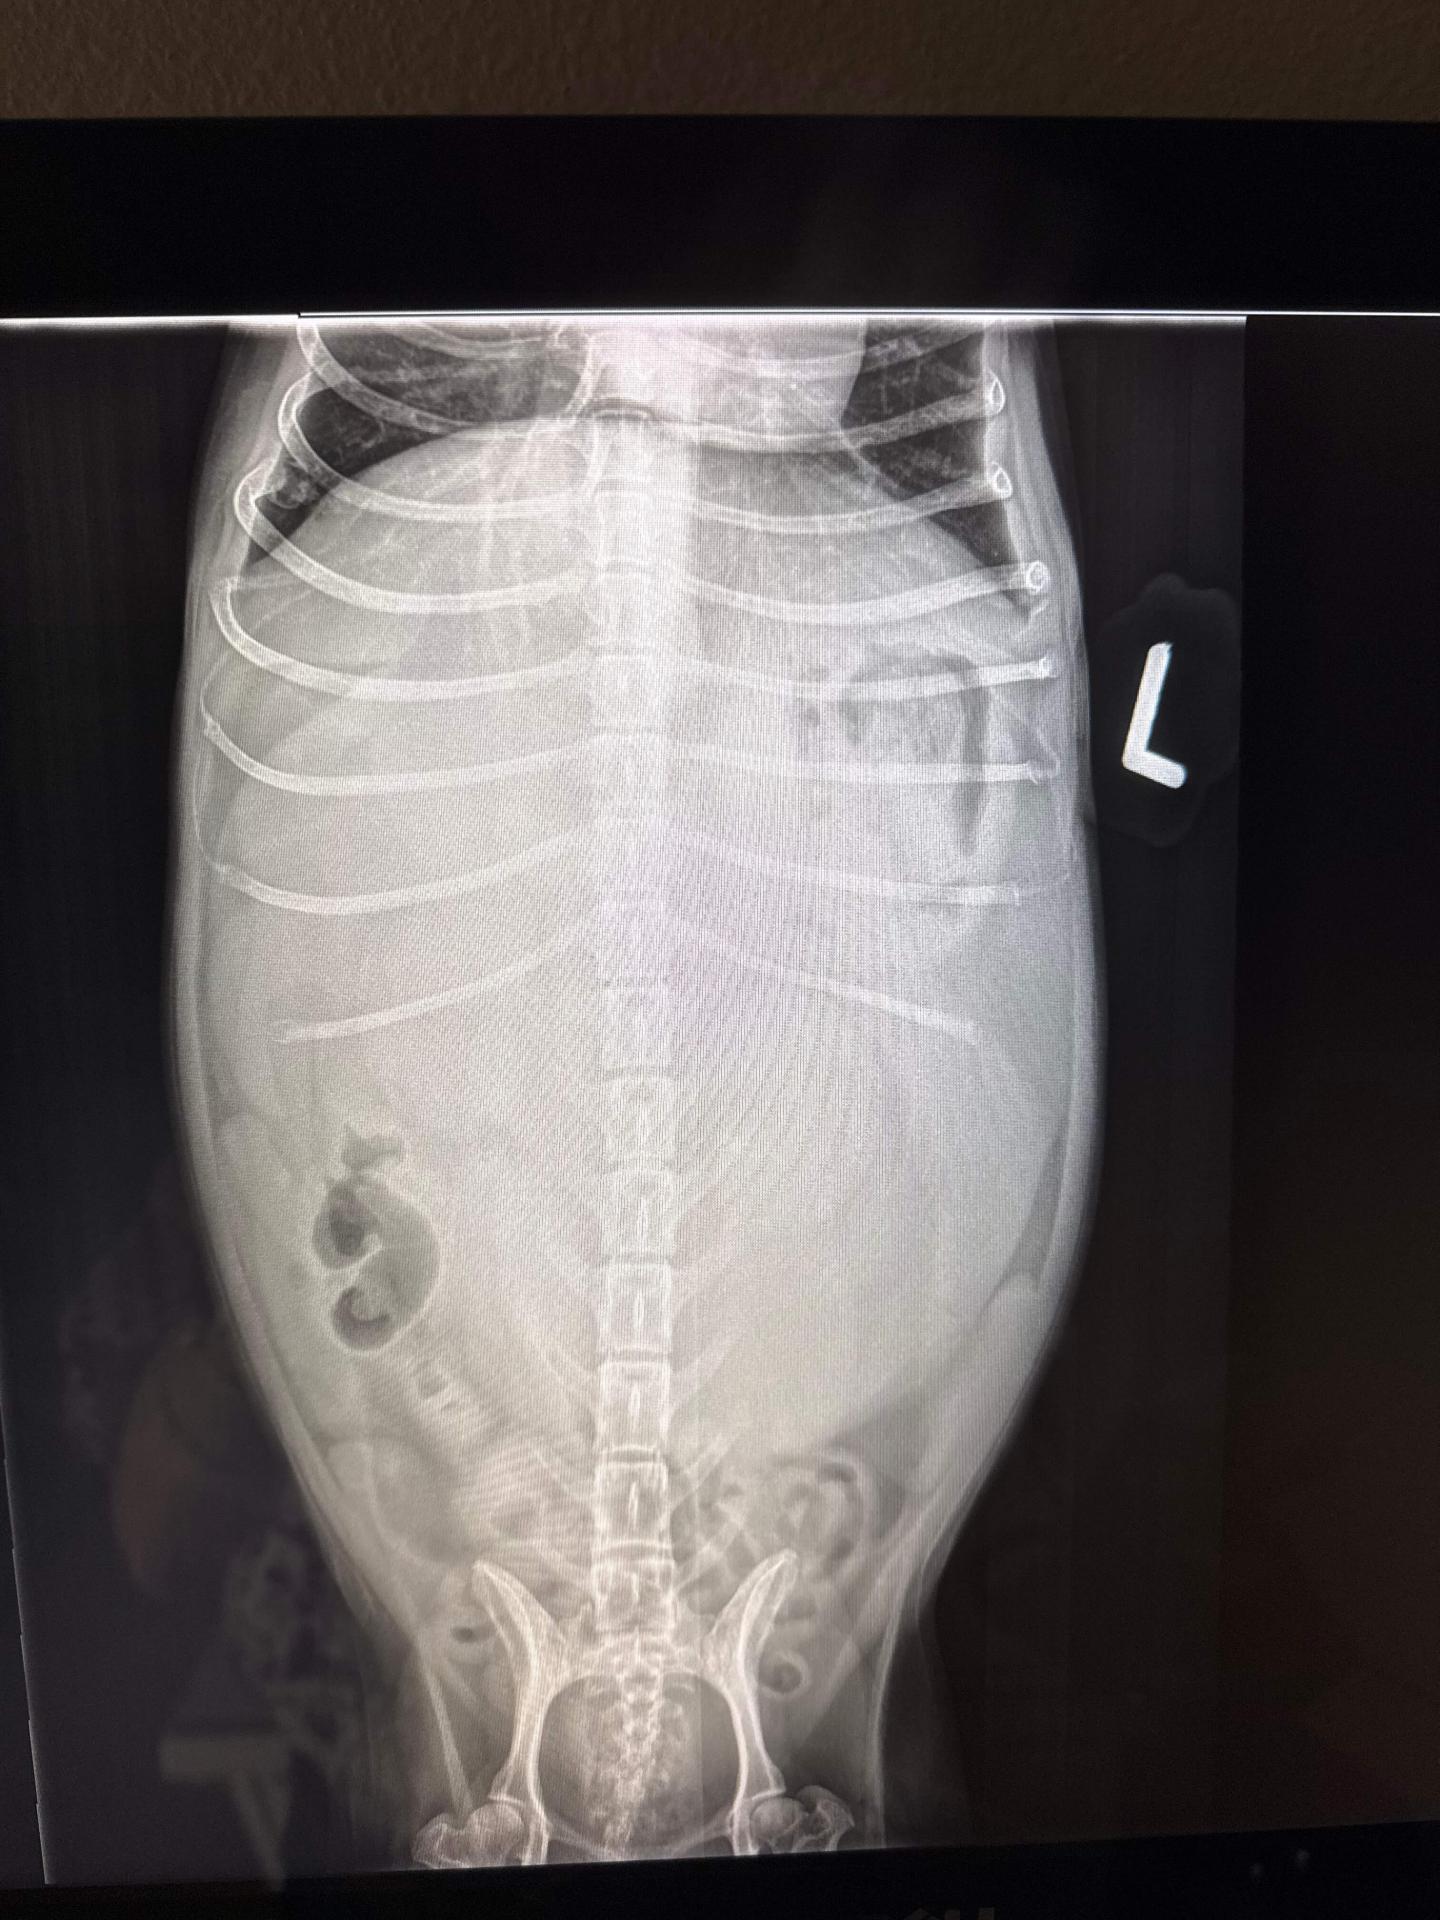

A 9 year old female spayed maltese presented for lack of appetite, weight loss and tremendously enlarged belly. She was also lethargic with reluctance to walk or jump.

Her examination showed a firm, pendulous abdomen with extreme muscle and fat loss over the remainder of her body. She was extremely weak and lethargic.

Imaging and labwork were performed to determine the source of the symptoms. A baseball-sized mass was identified in the abdomen, attached to either the liver or spleen.